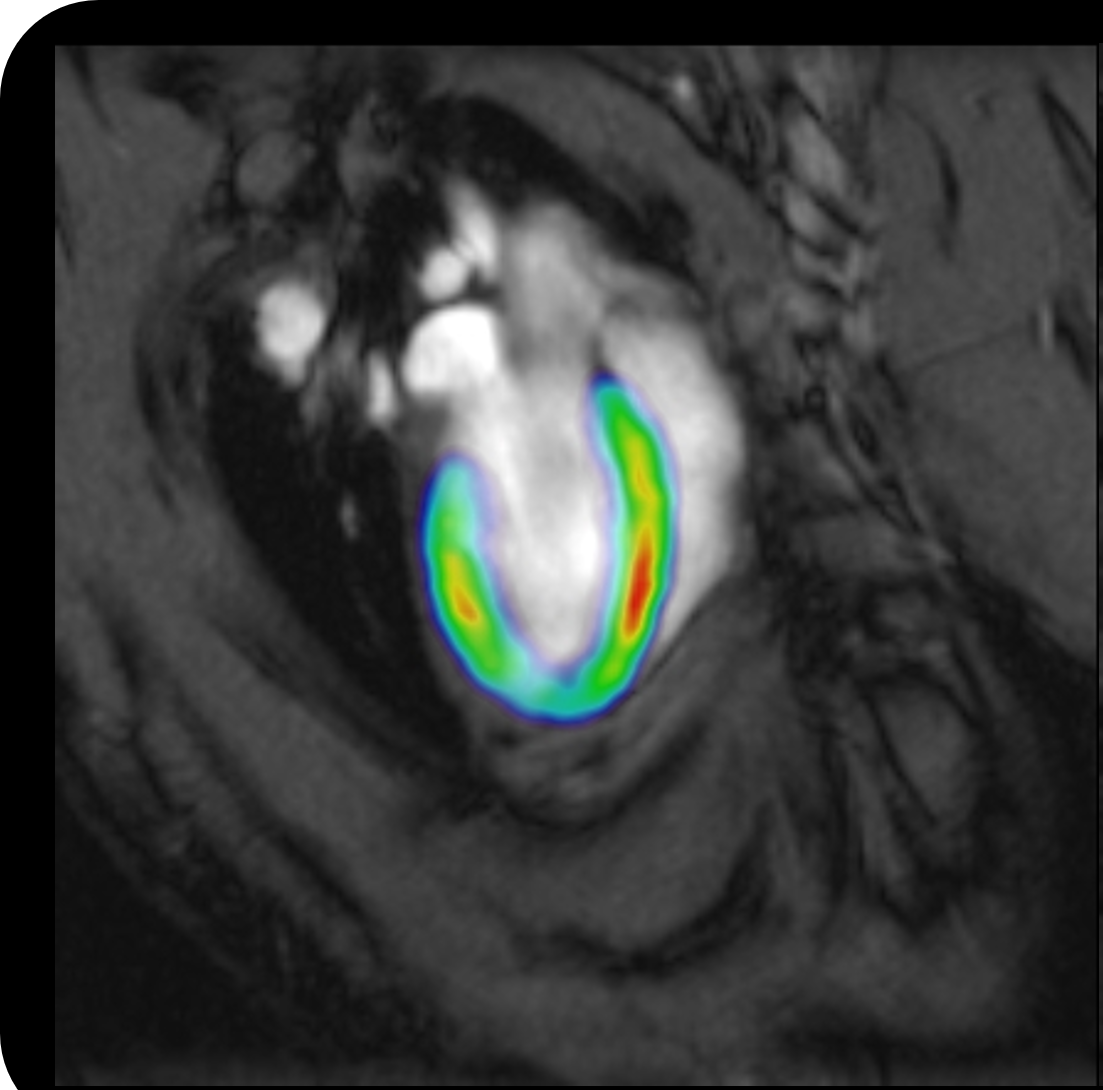

Thank you, and yes, we are very honored to host the 9th International CEST workshop at Emory this August. CEST provides a sensitive contrast for measuring tissue pH, proteins, and metabolites. It has already found broad applications in studying neurological, oncologic, and cardiovascular disorders. Meanwhile, our understanding of the CEST MRI contrast mechanism has steadily improved, collectively accomplished by chemists, physicists, experimentalists, and translational scientists. It is an exciting interdisciplinary field that is growing very rapidly.

Yes, you are right. Because proton exchange is pH dependent, CEST MRI is uniquely suitable to image pH. For example, pH MRI has been explored in mapping metabolic penumbra in ischemic stroke. Another hot area is mapping hypoxia as a new marker for tumor malignancy and plasticity, which often requires both endogeneous and exogeneous pH imaging approaches.